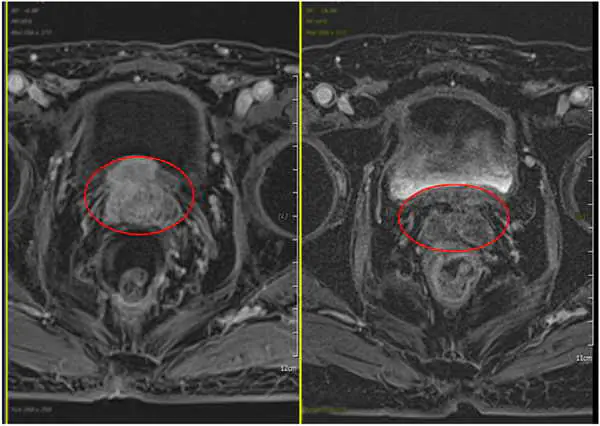

八年後,老台商解尿困難更加嚴重,到澄清醫院接受攝護腺切片化驗,診斷為攝護腺癌,癌症指數竟高達33.667(正常是小於4),再經核磁共振撿查,發現他的攝護腺癌為2.2公分×1.6公分,已穿透攝護腺表膜並侵犯上方的膀胱,決定接受抗賀爾蒙治療和快活光子刀放射線治療。

梁家郡醫師表示,患者每週五次,進行42次快活光子刀治療,完成療程後持續追蹤檢查,今年七月的核磁共振撿查結果,正式向老台商賀喜,他的攝護腺癌已完全消失不見,原本被穿透的攝護腺也完整恢復,癌症指數已降到0.025,幾乎驗不到癌細胞存在。

圖二:越南老台商治療前後圖(左圖紅圈腫瘤位置、右圖治療後腫瘤消失。